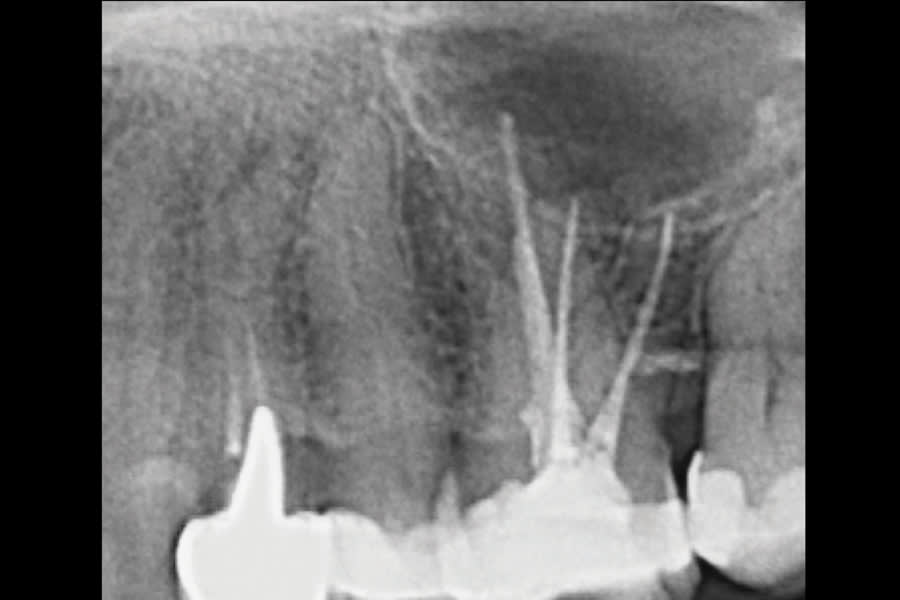

This case illustrates the value of contemporary reciprocating systems in addressing anatomical variations that can compromise primary endodontic success. A 62-year-old female patient was referred to the author’s practice due to persistent discomfort during mastication localized to the maxillary left first molar. Clinical examination revealed mild percussion sensitivity. A CBCT scan confirmed a previously untreated second mesiobuccal (MB2) canal and a periapical lesion associated with the mesiobuccal root. Thus, nonsurgical orthograde retreatment was chosen. Because the intricate morphology of MB2 canals can prove challenging for traditional rotary NiTi systems, the author has adopted the use of reciprocating single-file techniques, which offer enhanced safety. In this case, the author used the EdgeOne R Utopia™ R20 (EdgeEndo, edgeendo.com), a single-file reciprocating instrument designed for tight, calcified, and/or highly curved canals. Its S-shaped cross-section ensures cutting efficacy and fatigue resistance, while a proprietary heat treatment enhances both torsional strength and flexibility. The case was completed using standard irrigation protocols, followed by single-cone obturation with EdgeOne R Utopia™ gutta-percha points (EdgeEndo) and EdgeBioceramic™ Sealer (EdgeEndo) for a biocompatible and hermetic seal. Postoperative radiographs confirmed a well-centered fill and adequate canal debridement. The patient reported no significant postoperative discomfort and was asymptomatic within days.

EdgeOne R Utopia R20 successfully negotiated a narrow, double-curved MB2 canal without the need for glide path preparation or multi-instrument techniques. The reciprocating motion reduces continuous torsional stress, improves resistance to cyclic fatigue, and preserves canal anatomy.

The case was completed using a true single-file technique, reducing chairtime and preserving conservative canal shaping.